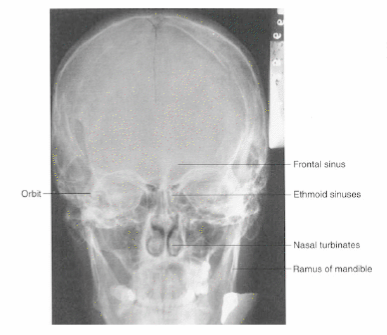

Name the radiologic view of the skull shown below?

What is a Caldwell (PA) view of the skull?